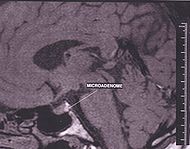

Диагностика опухоли гипофиза при синдроме Нельсона затруднена. Кортикотропиномы являются часто микроаденомами и длительное время, располагаясь внутри турецкого седла, не нарушают его структуры. При небольших аденомах гипофиза при синдроме Нельсона турецкое седло по размерам находится на верхней границе нормы или незначительно увеличивается. В этих случаях его детальное изучение на боковых краниограммах и рентгенограммах с прямым увеличением, а также томографическое исследование позволяют распознать ранние симптомы развития опухоли гипофиза. Диагностика развившейся и большой аденомы гипофиза не представляет сложности. Развившаяся аденома гипофиза обычно характеризуется увеличением размеров турецкого седла, выпрямлением, истончением или разрушением стенок. Разрушение клиновидных отростков, углубление дна седла свидетельствуют о растущей опухоли гипофиза. При большой опухоли наблюдается расширение входа в турецкое седло, укорочение клиновидных отростков, появляются симптомы, характерные для супра-, анте-, ретро- и интроселлярного расположения опухоли. При применении дополнительных методов исследования (томографии при пневмоэнцефалографии, флебографии кавернозного синуса и компьютерной томографии) можно получить более точные данные о состоянии турецкого седла и расположении опухоли гипофиза за его пределами.